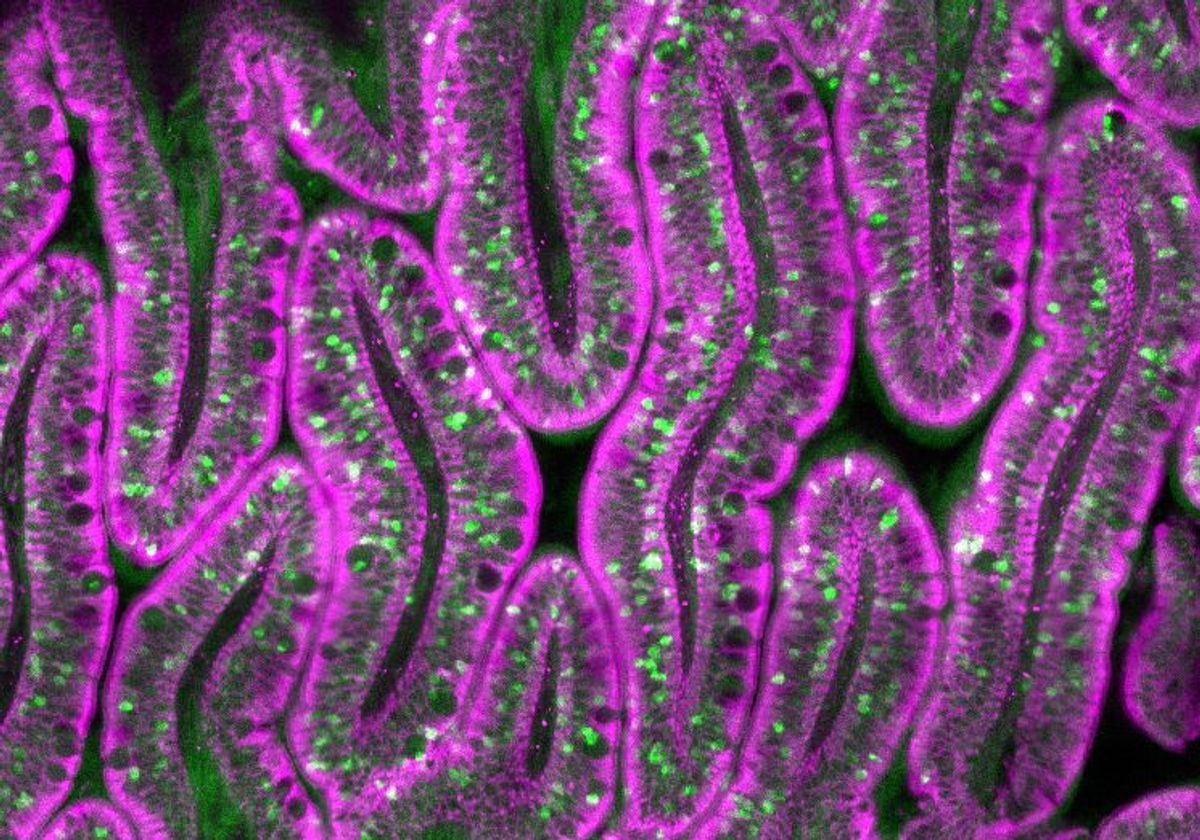

Cell calling